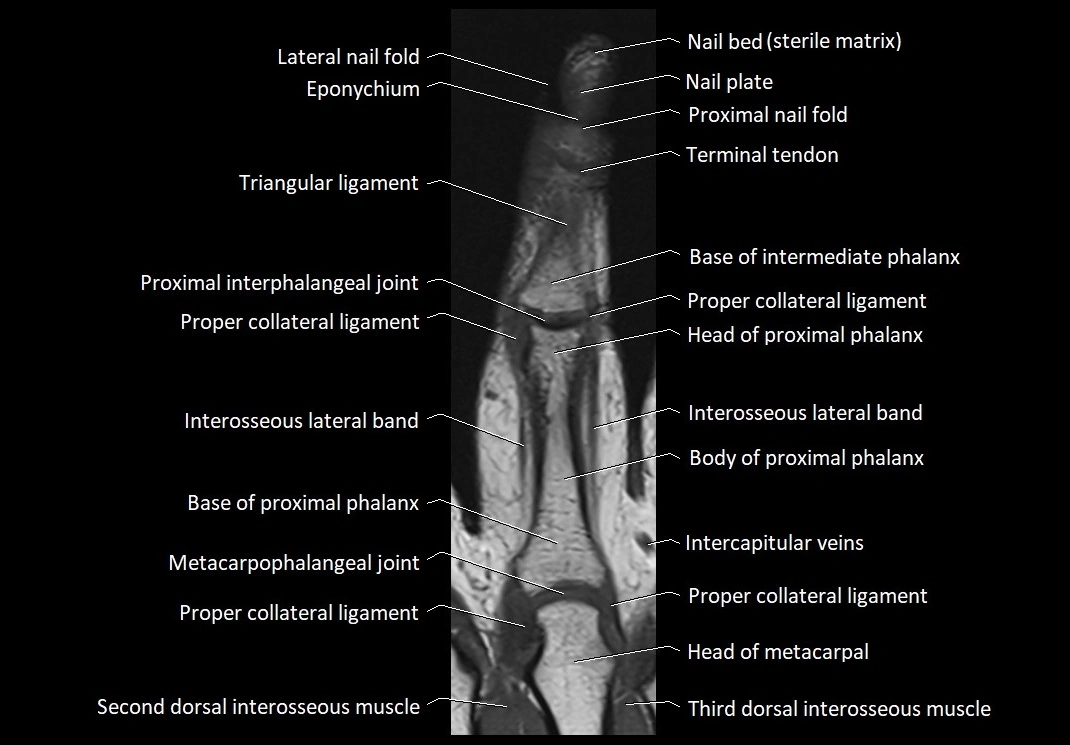

MRI images

image